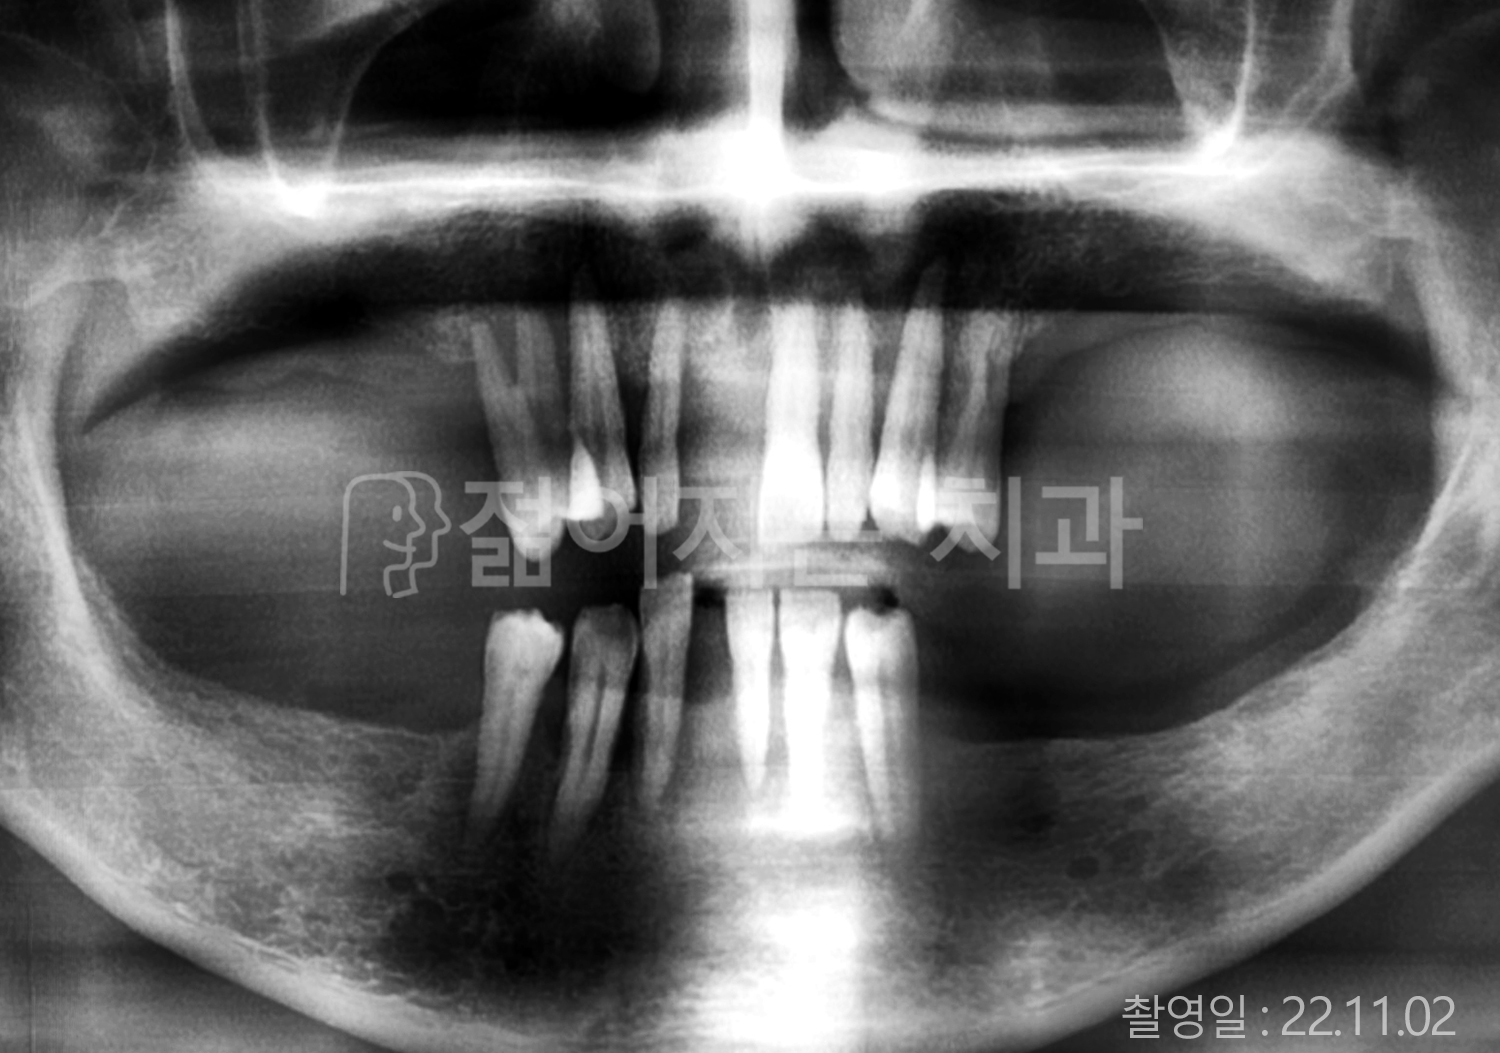

• 50대 전체치아 10개 이상 임플란트

• 50대 고혈압, 고지혈증 전체치아 10개 이상 임플란트